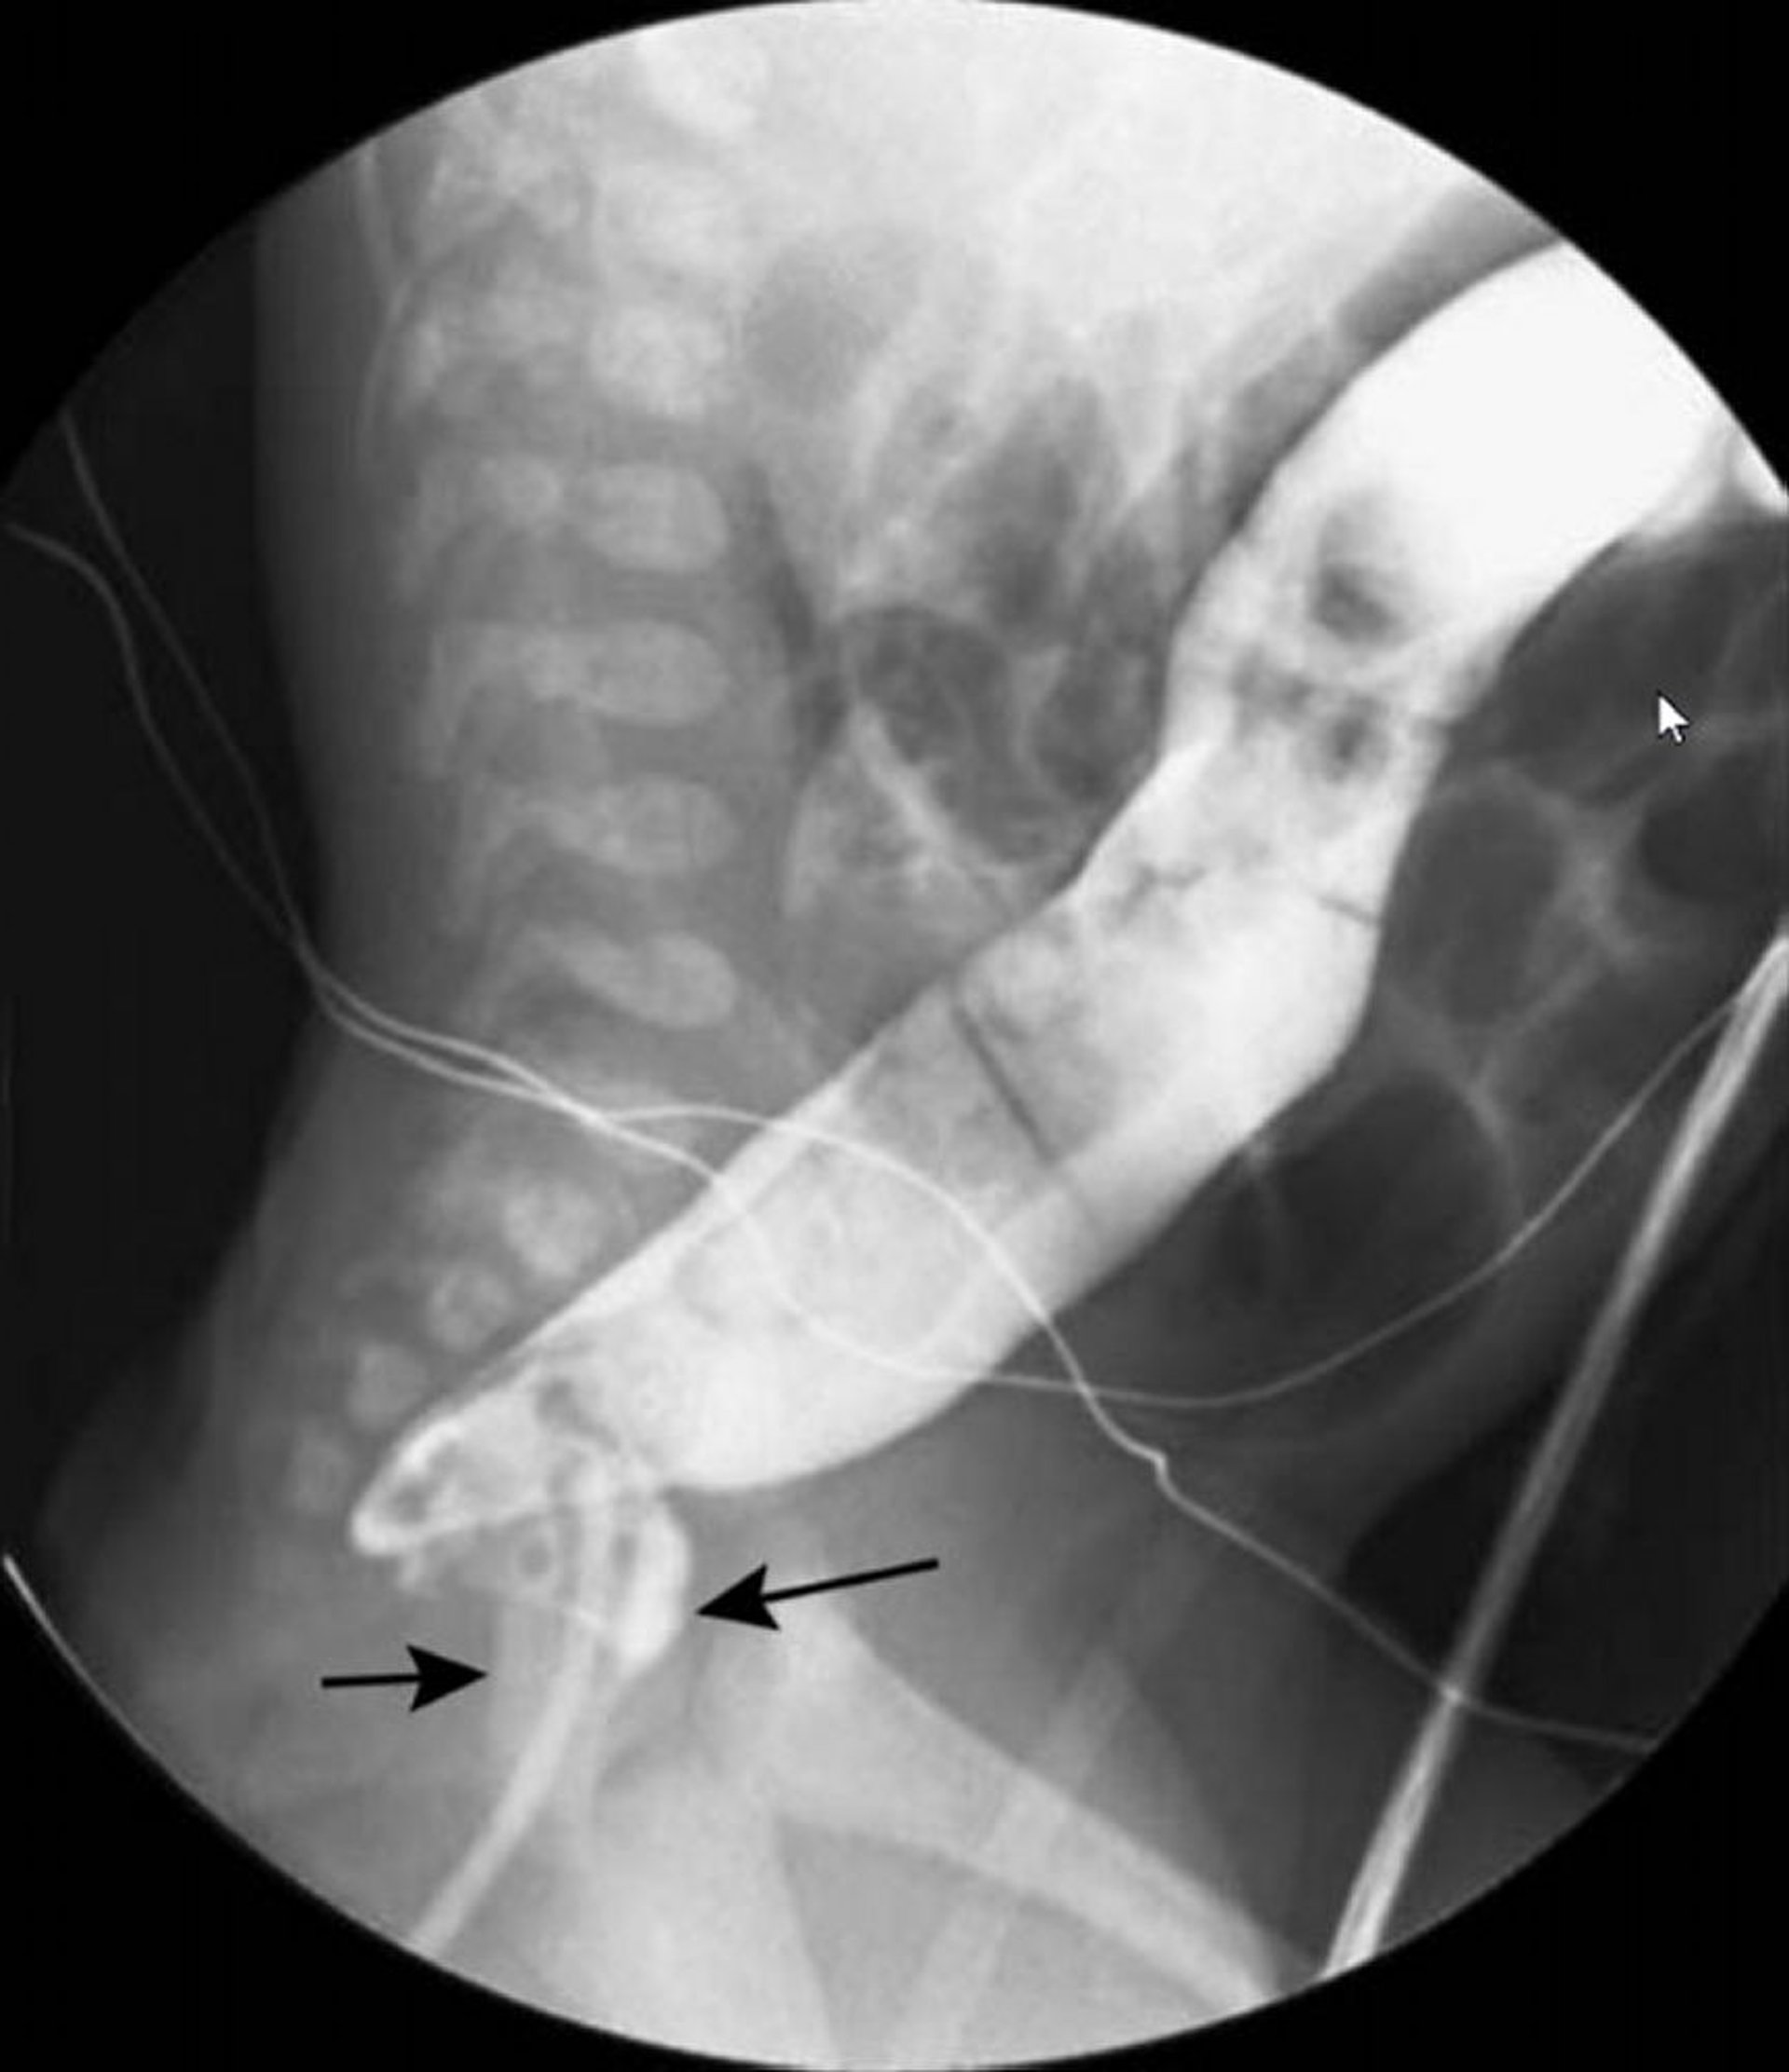

Bariumeinlauf mit Einzelkontrast, der das Schwanenhals-Erscheinungsbild der Hirschsprung-Krankheit zeigt

Auf dieser Abbildung zeigt der Bariumeinlauf ein verengtes Rektum (schwarze Pfeile) und ein erweitertes Kolon (weißer Pfeil) weiter proximal.